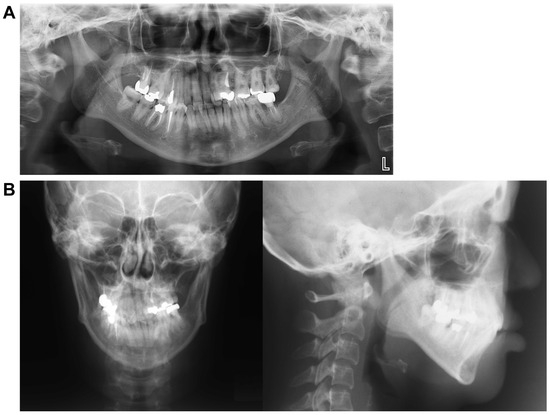

5.3. Panoramic Cephalometric Radiograph (Figure 9D)

The roots of the teeth appeared parallel, indicating good overall parallelism. Furthermore, a carious-like radiolucency was observed distal to the left mandibular second premolar. At the patient’s request, retention was performed before the placement of a prosthetic restoration for the left mandibular second molar. Therefore, there are plans to proceed promptly with prosthetic restoration soon.

5.4. Lateral and Frontal Cephalometric Radiographs (Figure 9E)

The SNA increased slightly from 73.0° to 75.0°, indicating a slight forward positioning. However, the SNB decreased from 72.0° to 70.0°, suggesting a posterior positioning of the Mand.P with a clockwise rotation, leading to an increase in the mandibular plane angle from 35.0° to 37.0°. Frontal cephalometric radiography showed that the cant had resolved, with the Menton and facial midline nearly aligned. In addition, the deviations of the maxilla and mandible improved, resulting in a symmetrical facial appearance.